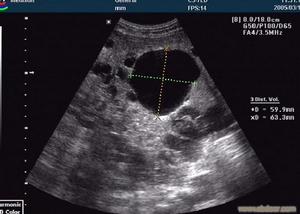

多囊腎 超聲檢查 |

5、超聲檢查:超聲影象用於多囊腎的診斷優於排泄性尿路造影及腎核素檢查。

多囊腎的診斷一般不難,臨床上可根據家族遺傳病史(父母、兄弟、姐妹、子女有多囊性疾病等),雙側腎臟腫大和蛋白尿作出診斷,超聲顯像檢查對確診起決定作用。腹部可見腎臟輪廓不整齊,呈不規則增大。超聲顯像可見雙腎明顯增大,腎內布滿大小不等的液性暗區,正常腎臟結構消失。此外靜脈腎盂造影或逆行腎盂造影對診斷也有所幫助,可見腎盂被拉長,腎盞變平或呈半月狀。早期可能只見一側有改變,但到晚期常可因腎功能不全而不顯影,須進行大劑量靜脈腎盂造影方能明確診斷。大部分患者早期就已有腎臟濃縮功能的改變,如尿比重降低、尿滲量降低,以及尿量明顯增多;晚期則出現腎功能不全和尿毒症。

多囊腎 超聲檢查